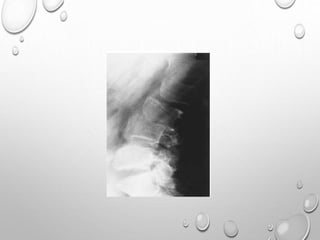

Spine radiographs reveal classic sandwich vertebrae of osteopetrosis (red

arrows). This is manifested as thickening and sclerosis of the vertebral endplates,

and of the bone adjacent to the endplates.

There is also marked thickening of the posterior vertebrae (yellow arrows),

especially in the vertebral arch.

Lateral radiograph of the skull reveals diffuse thickening of the calvarium,

most significant in the region of the occiput. The partially visualized upper

cervical vertebrae and maxilla are also dense and thickened.